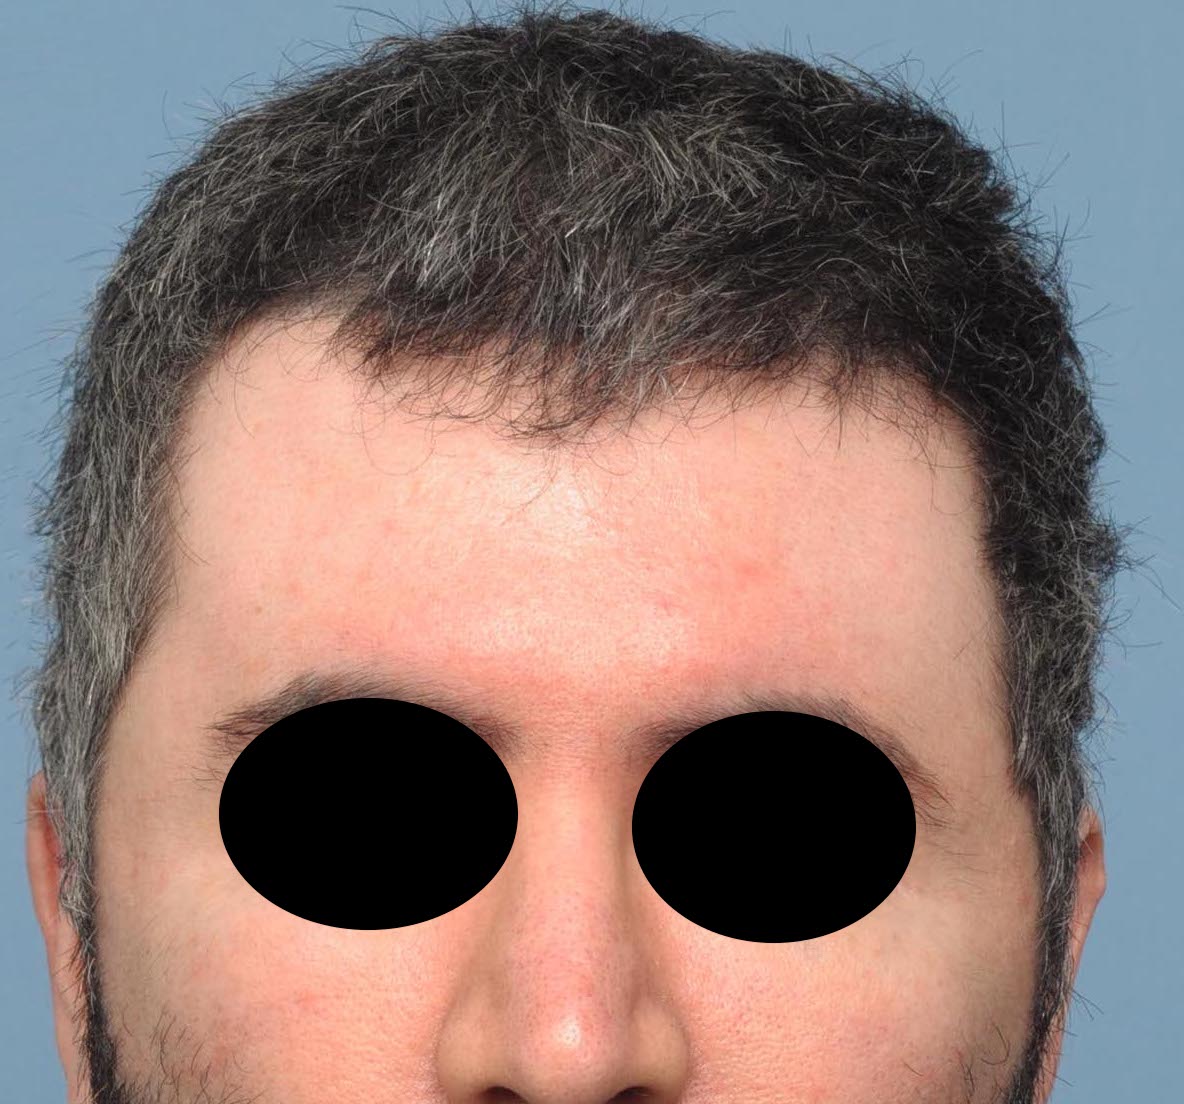

Desire for change of head shape from front view form an inverted V shape to a rounder and wider head shape.

Placement of custom extended forehead-temporal implants through incisions in the crease behind the ear. (he had a prior back of head skull implant which is green in the implant designs and which the head widening implants partially covered it)

Desire for change of head shape from front view form an inverted V shape to a rounder and wider head shape.

Placement of custom extended forehead-temporal implants through incisions in the crease behind the ear. (he had a prior back of head skull implant which is green in the implant designs and which the head widening implants partially covered it)